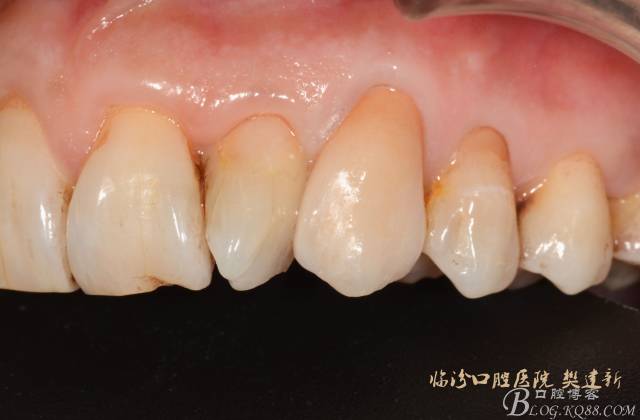

圖10  修復(fù)體代入口內(nèi)照

640 (9).jpg

圖12 修復(fù)體代入口內(nèi)正面照

640 (11).jpg